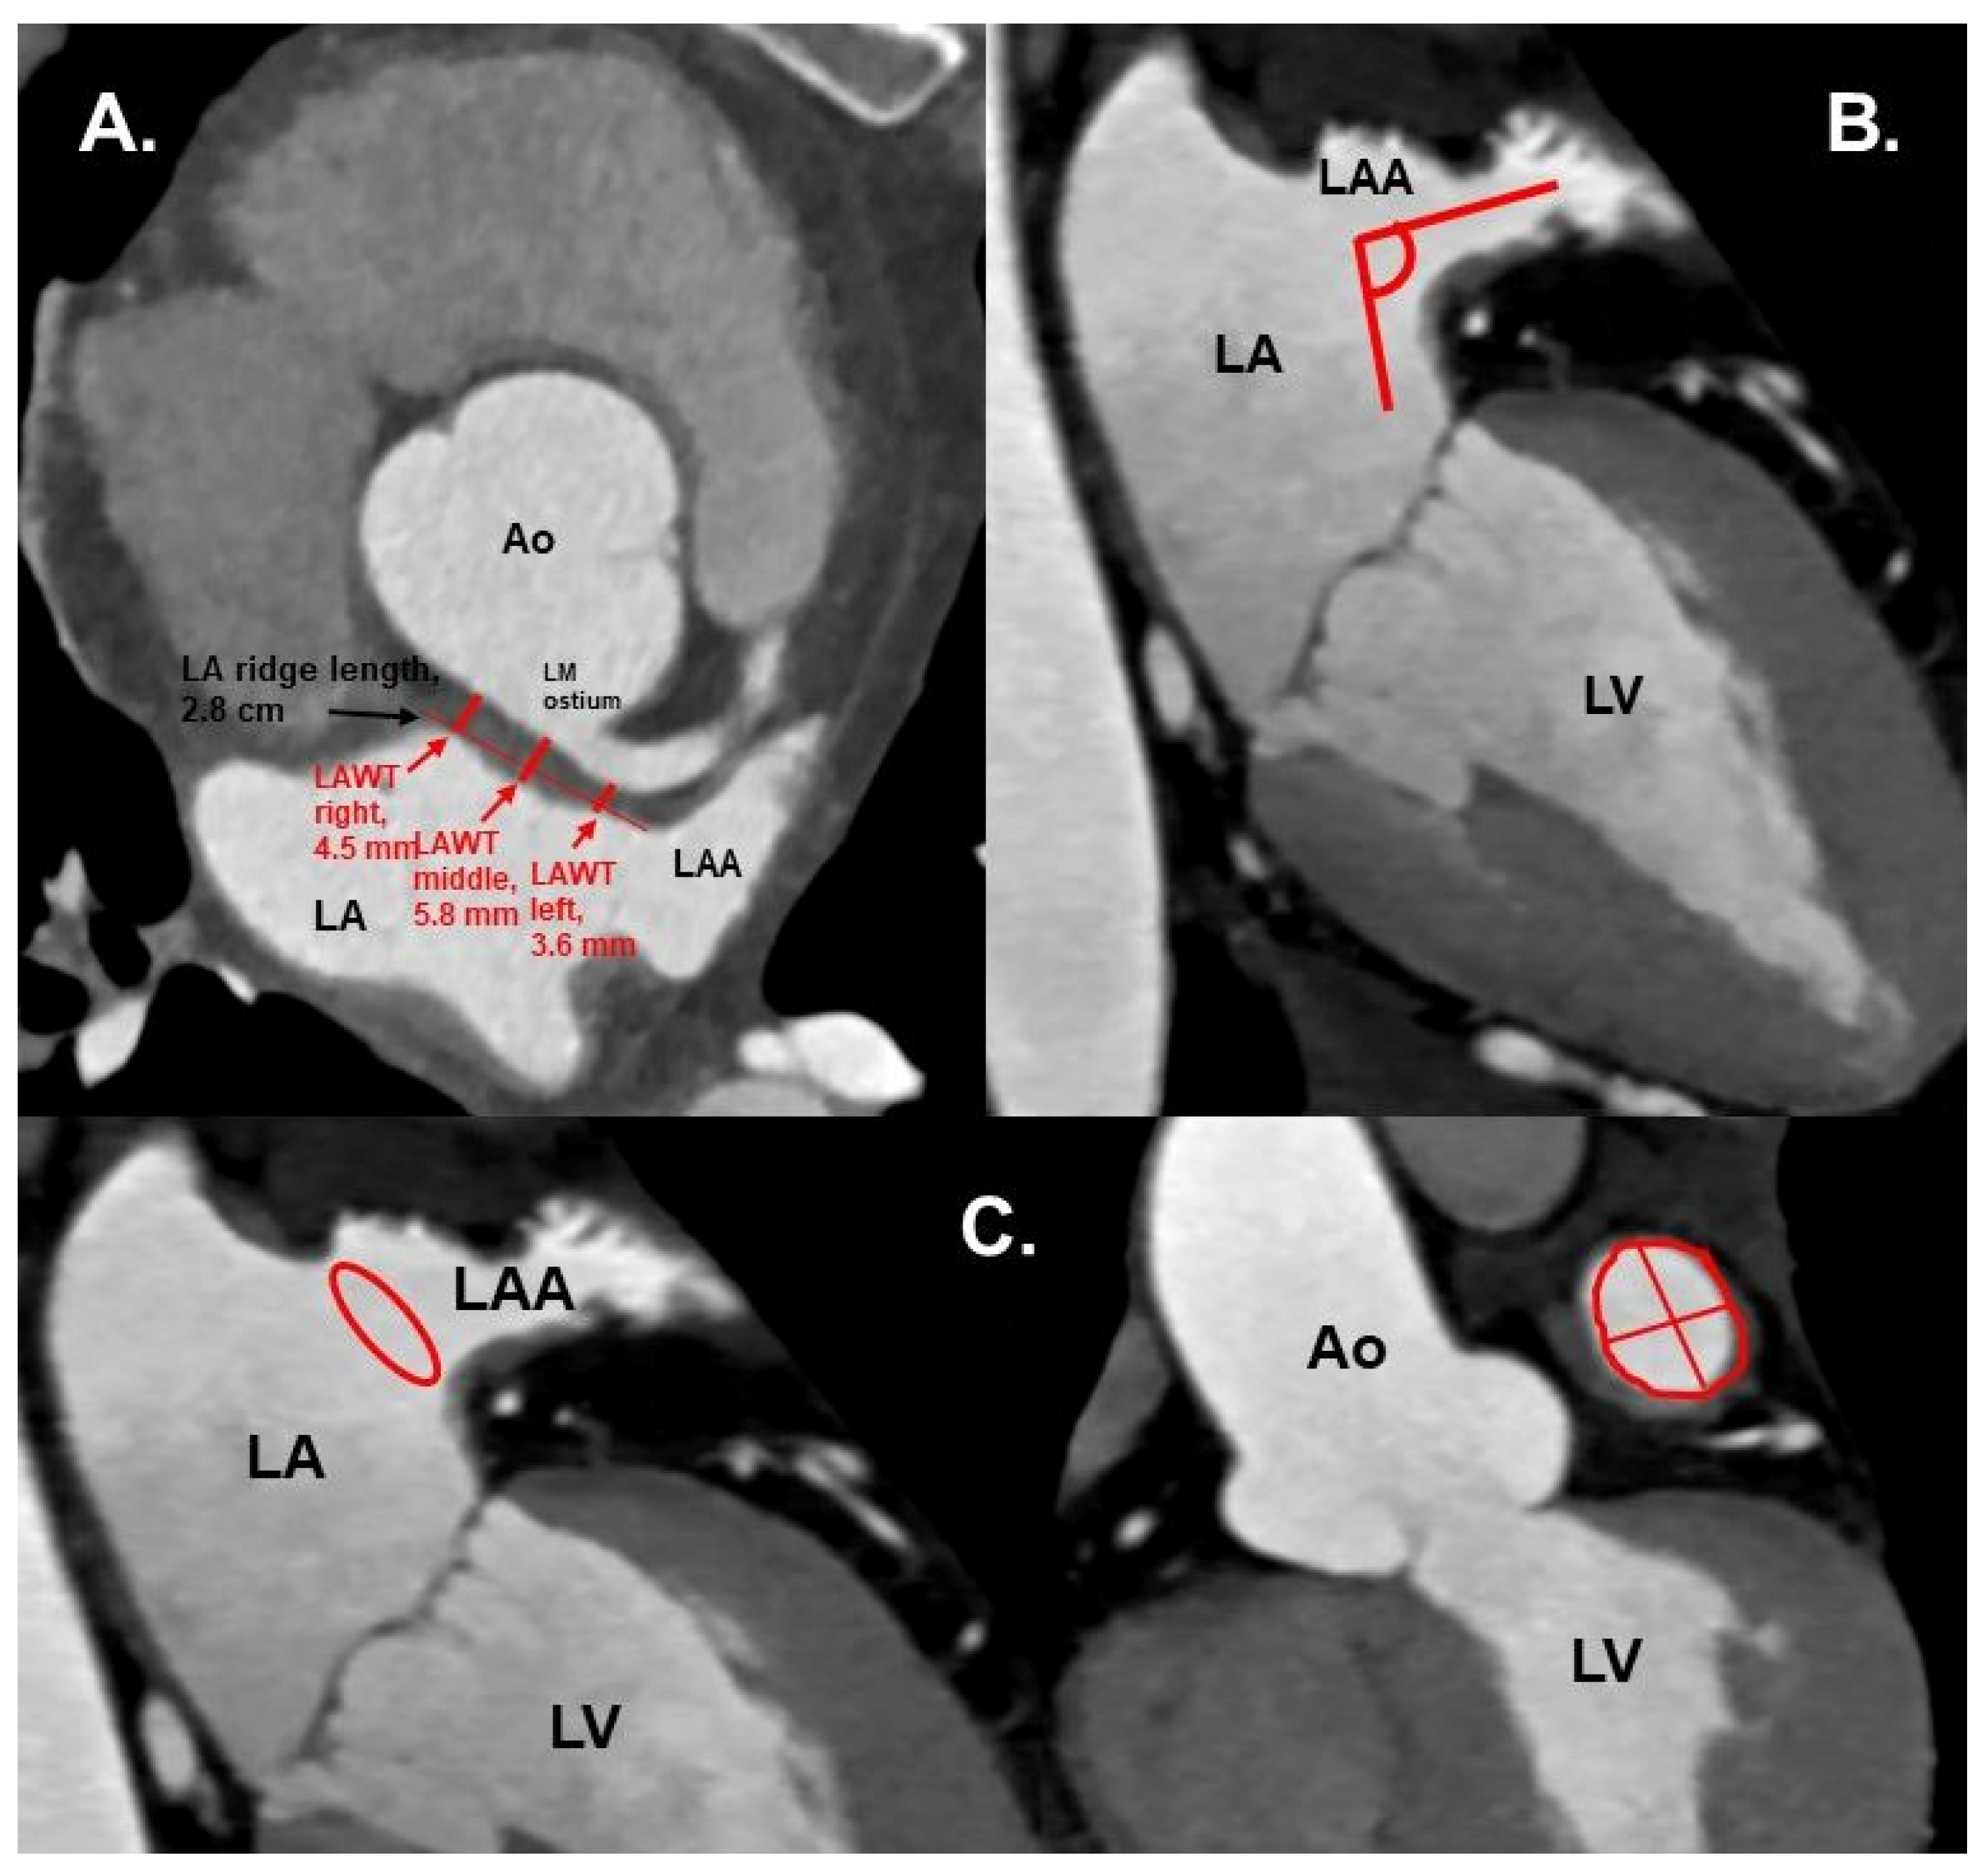

Figure 2. (A) CTA 3D-VRT reconstruction of LAA with a sharp tip angulation (≤90°) (black arrow). (B) sagittal plane with red arrows delineating sharp LAA tip angulation. Ao—aorta, LA—left atrium, LAA—left atrial appendage. - Left atrial anterior wall thickness (LAWT), also called LA ridge, was measured at three points antero-posteriorly (left—being the closest point to the LAA ostium, middle and right—the point of the LA anterior wall, which is most distant to the LAA) and the mean of the three points was calculated; LA ridge length was defined as the medio-lateral length of the LA ridge. These parameters were measured in axial plane at the left main (LM) coronary artery ostium and LAA ostium level using a digital caliper (Figure 3a).

Figure 3. (A) Cardiac CTA: axial plane. Red arrows show the LAWT measurements at the left, middle and right points, and the LA ridge length. Measurements were taken at the plane of left main coronary ostium. (B) CTA: axial oblique plane, showing LAA ostium angulation (red lines) to orthogonal plane. (C) CTA with axial oblique planes of the heart. Left: LAA ostium area shown in red circle. Right: LAA ostium area (red circle), length and width (red lines). Ao—aorta, LA—left atrium, LAA—left atrial appendage, LAWT—left atrial wall thickness, LM—left main coronary artery, LV—left ventricle. - Number of LAA lobes using 3D—VR according to Abbara et al. [13]

LAWT in the middle, right parts and the mean of all three parts (left, middle, and right) were associated with CE stroke on univariable analysis (OR 1.8; CI: 1.24–2.62, p = 0.002, OR 1.55; CI: 1.08–2.21, p = 0.017 and OR 1.68; CI: 1.05–2.71, p = 0.032, respectively), as well as after adjusting for CHA2DS2-VASc score and LA diameter in the multivariable regression model (OR 1.94; CI: 1.26–3.0, p = 0.003 and OR 1.57; CI: 1.07–2.31, p = 0.021, respectively), whereas the mean LAWT only showed a borderline significant association (OR 1.66; CI: 1.0–2.75, p = 0.052).

A greater LAWT in the middle and right parts was independently associated with CE stroke. The mean of the three points (left, middle, and right) showed a borderline association, which supports the concept of positive left atrial wall remodeling in AF, since a greater LAWT indirectly signals remodeling of LA [18]. Since LAWT in principal has a high variation along the entire wall, our data identified two specific measurement sites (middle and right part) as the best points highest predictive for CE stroke, whereas the mean was not as powerfully associated with stroke.